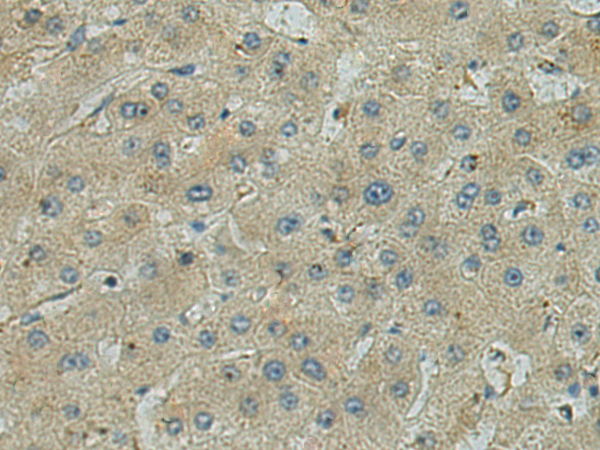

分类: 科研抗体货号: P12120别名: CDR; ETO; MTG8; AML1T1; ZMYND2; CBFA2T1应用: IHC反应种属: Human, Mouse